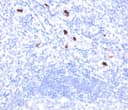

Myeloid Cell Marker Antibody

This antibody recognizes a 183kDa protein with DNA-binding characteristics, which is identified as a myeloid cell specific antigen. Clone BM-1 antibody reacts with myeloid precursor cells and granulocytes in bone marrow. Its antigen appears to be restricted to M2 and M3 acute myelogenous leukemia (AML) subtypes. This type of marker is useful in the identification of different levels of cellular differentiation. BM-1 and BM-2 antibodies react with early precursor and mature forms of human myeloid cells. This mAb is useful in the identification of myelogenous leukemias, distinguishing granulocytic sarcomas from lymphoid malignancies and also in the study of differentiation and transformation of human myeloid cells. The biological function of the marker protein is not clear, although it has been proposed that it may play a role in cell differentiation.Host:

FACS, IF, IHC-PFormat: